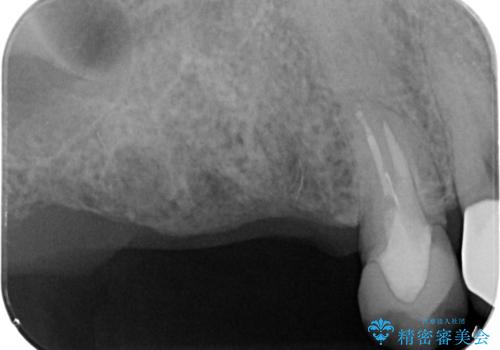

- 歯を抜いたまま放置してしまい、「やはりしっかりと噛めるような状態にしてほしい」とインプラント治療を希望され来院されました。

人工歯根であるインプラントを埋入することで奥歯でまたしっかりと噛める咬合機能を回復します。